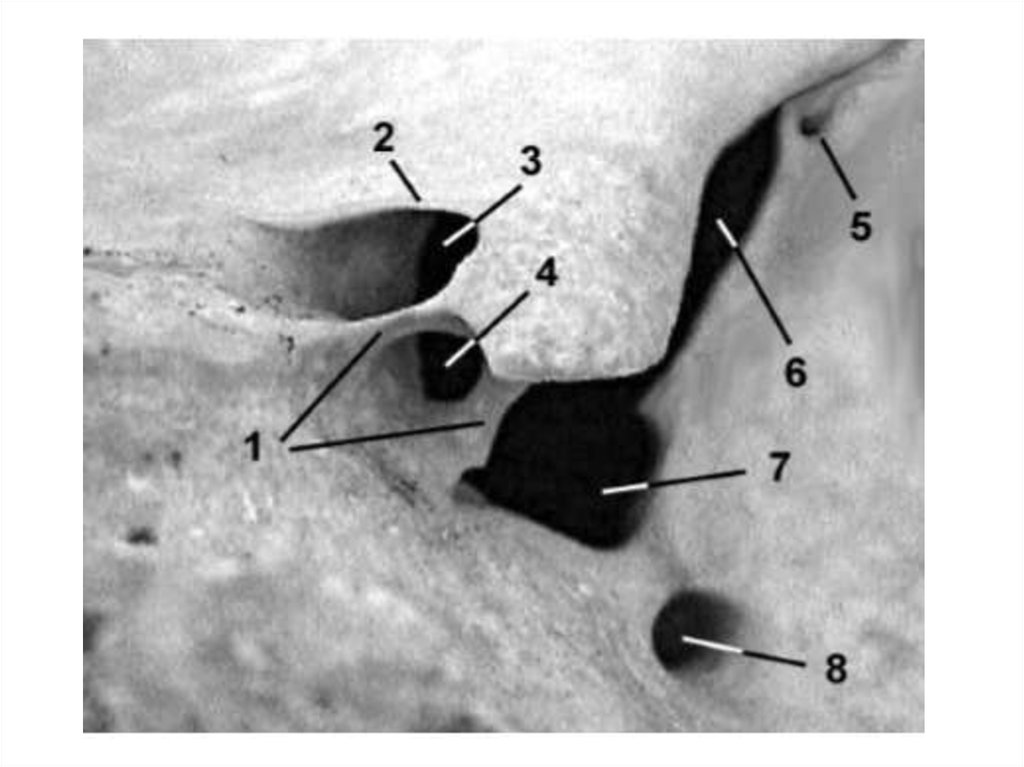

ВНУТРЕННЕЕ СЛУХОВОЕ ОТВЕРСТИЕ

внутренний слуховой проход

Содержимое:

• лицевой нерв;

• преддверно-улитковый нерв.

ПОДДУГОВАЯ ЯМКА

• отросток твердой мозговой оболочки;

• мелкие сосуды.

НАРУЖНАЯ АПЕРТУРА ВОДОПРОВОДА ПРЕДДВЕРЬЯ

• эндолимфатический проток.